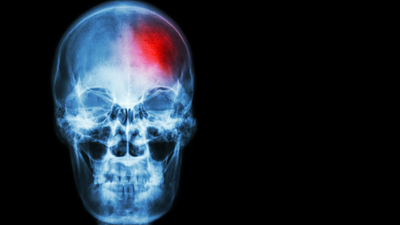

"Sıcak hava, beyin kanaması riskini artırıyor"

Beyin kanaması; beyindeki kan damarlarının yırtılması sonucu, kanın beyin dokusuna sızmasıyla meydana gelen ciddi bir sağlık sorunudur. Bu durum, beyinde basınç artışına ve beyin hücrelerinin zarar görmesine yol açar. Beyin kanaması, felç, konuşma bozuklukları, hafıza kaybı ve hatta ölüm gibi ciddi sonuçlar doğurabilir.